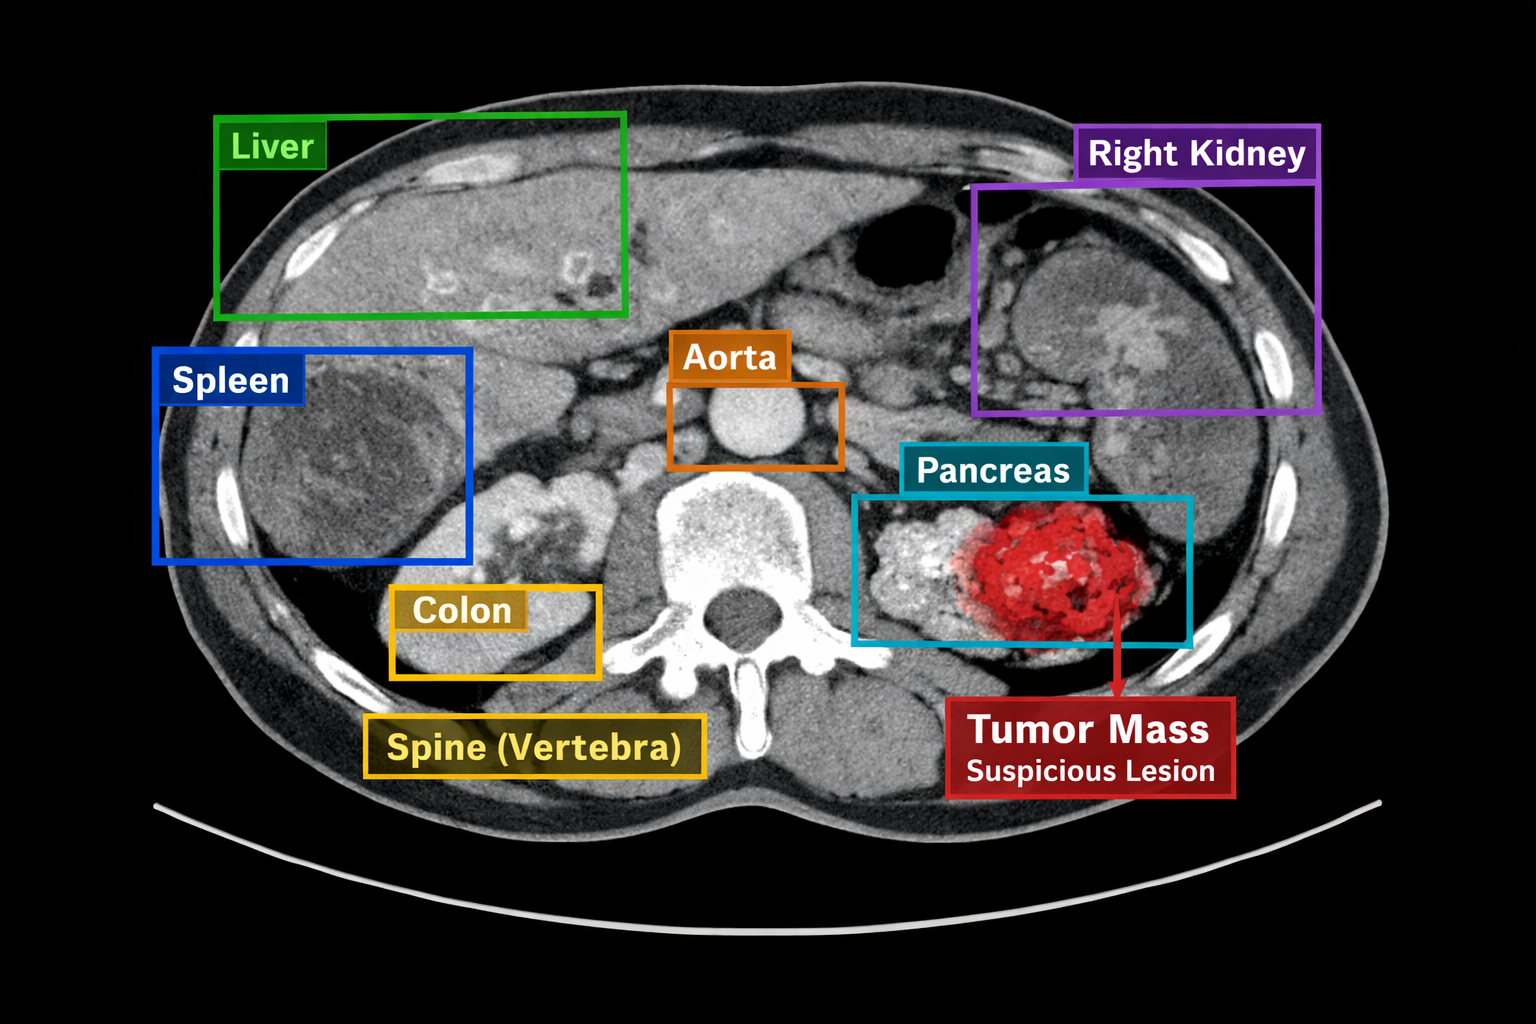

Medical Image Annotation

Classification, bounding boxes, and segmentation for radiographs, MRIs, and CT scans.